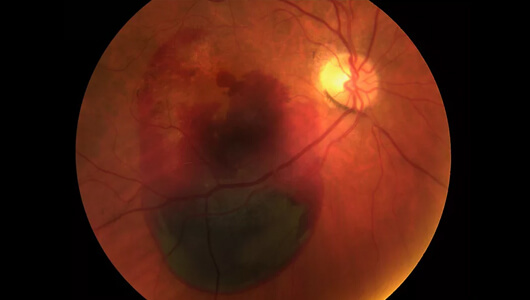

Evo slike mrežnjače još jednog pacijenta - 27-godišnjeg programera koji je došao da ukloni astigmatizam pomoću laserske operacije.